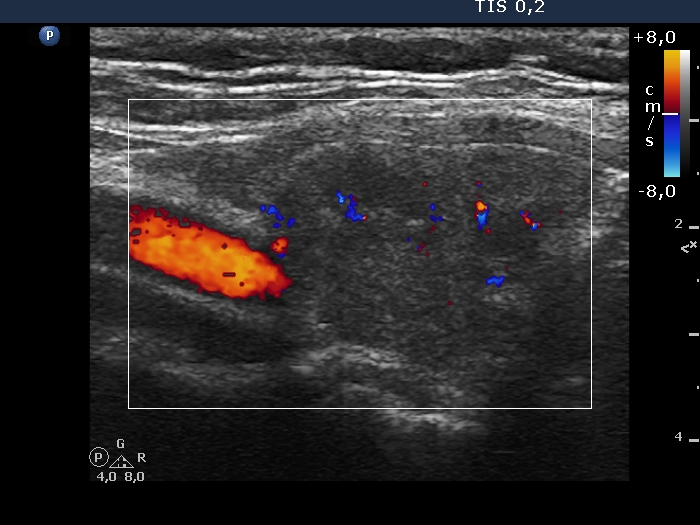

Examination in 2020 (third row of images):

Comment. This story draws attention to how important it may be to be aware of the results of a previous study. By result I do not mean the findings, but the archived recordings.Clinical data: The patient came to a routine follow-up. She had no complaints.

Palpation: Both lobes were a bit firm on palpation. There was a not firm nodule in the right lobe.

Laboratory test: TSH 3.38 mIU/L on daily 125 microgram levothyroxine.

Ultrasonography. The previously cystic lesion has spontaneously decreased in size, the cystic fluid has disappeared. However, the hyperechogenic foci were still visible. If we had only seen this current study, we would have had to regard these echogenic granules microcalcifications.

We recommended that she takes the replacement therapy at the same dose and has a TSH scan after a year and an ultrasound scan after three years.